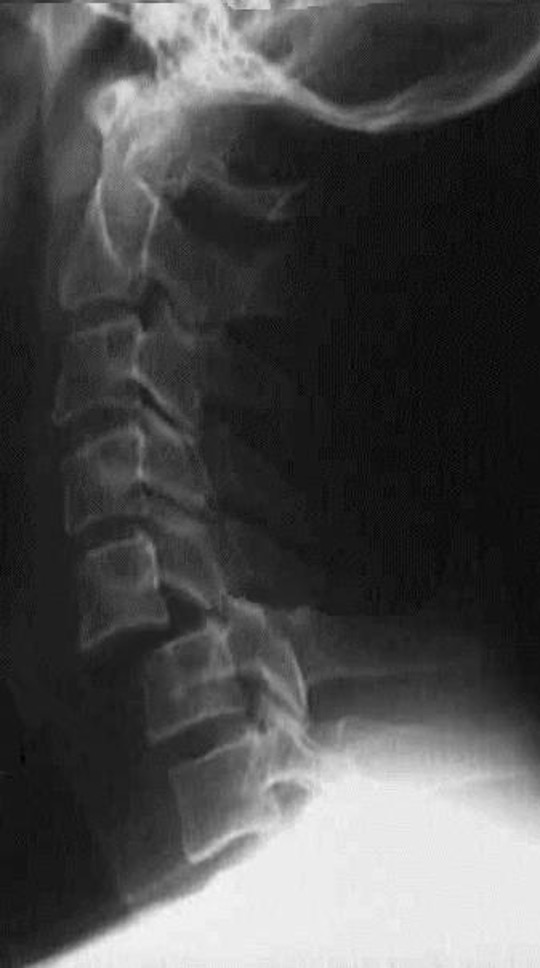

Unilateral facet joint dislocation on xray - 25% subluxation on lateral X-ray (<50%)

>50% forward subluxation